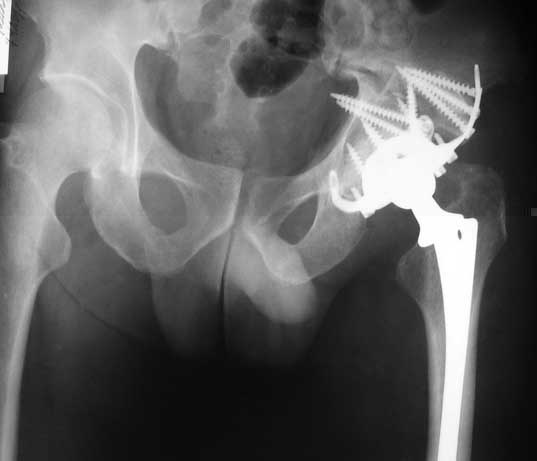

In such cases we use hip arthroplasty with "Octopus" acetabular system (De Puy). This system consist of acetabular ring and cementless cup.

It`s allow you to fix the reinforcement ring in proper position, then bone grafting of the defects of the acetabulum walls and floor.

Then you fix the cup to the ring.

I will show some cases.